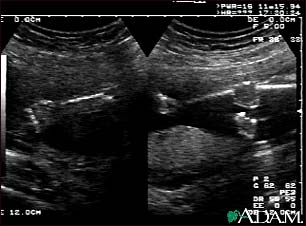

Ultrasound, normal fetus - arms and legs

This is a normal fetal ultrasound performed at 19 weeks gestation. This is the type of spilt-screen display you might see during an ultrasound, or if the technician prints a copy of the ultrasound for you. This ultrasound shows both the left arm (seen in the left side of the display), and the lower extremities (seen in the right side of the display). The white areas of the arm or legs is developing bone.